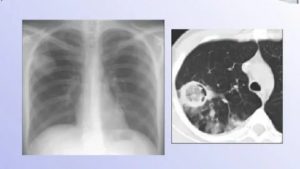

Диагностика микоза легких проводится врачом-пульмонологом, к которому нужно обратиться сразу после выявления симптоматических проявлений грибкового заболевания.

Дальнейшая симптоматика и исследования мокроты в клинической лаборатории определят диагноз. Врачи на основании результатов, установят название болезни: пневмония, туберкулёз, рак легкого или другие, и определяют степень поражения лёгких и основные места локализации плесени.